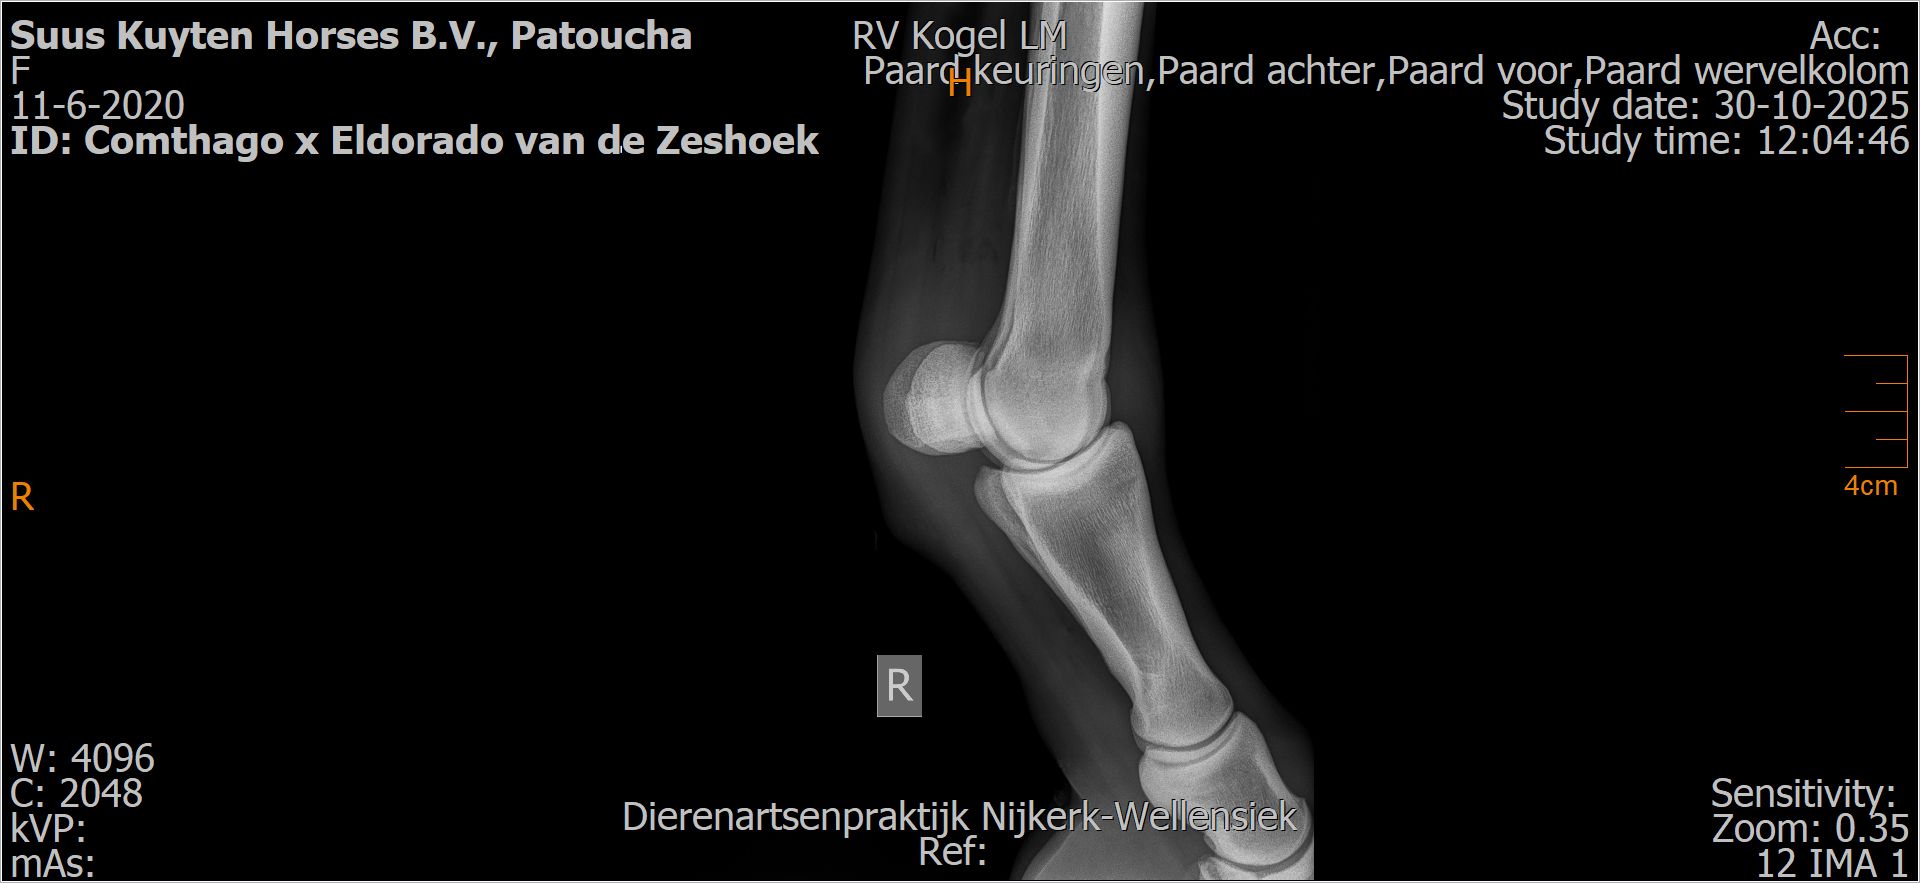

Patoucha

Leeftijd:

7

Röntgenfoto’s